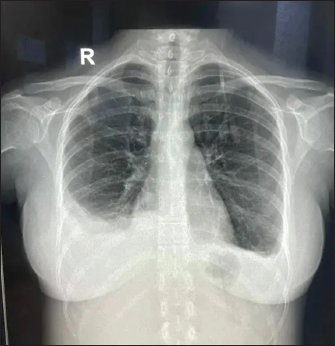

Inflammatory workup revealed: ESR–22 mm Hg in 1 hour, CRP–53.2 mg/dl, Procalcitonin–1.92 ng/ml. D dimer–1.9 mg/l. Ferritin–2,500 ng/ml. Chest X-ray revealed blunting of bilateral costophrenic angles suggestive of bilateral pleural effusion (Fig. 1).

Fig. 1. X-ray showing blunting of bilateral costophrenic angles (Right > left) suggestive of pleural effusion.